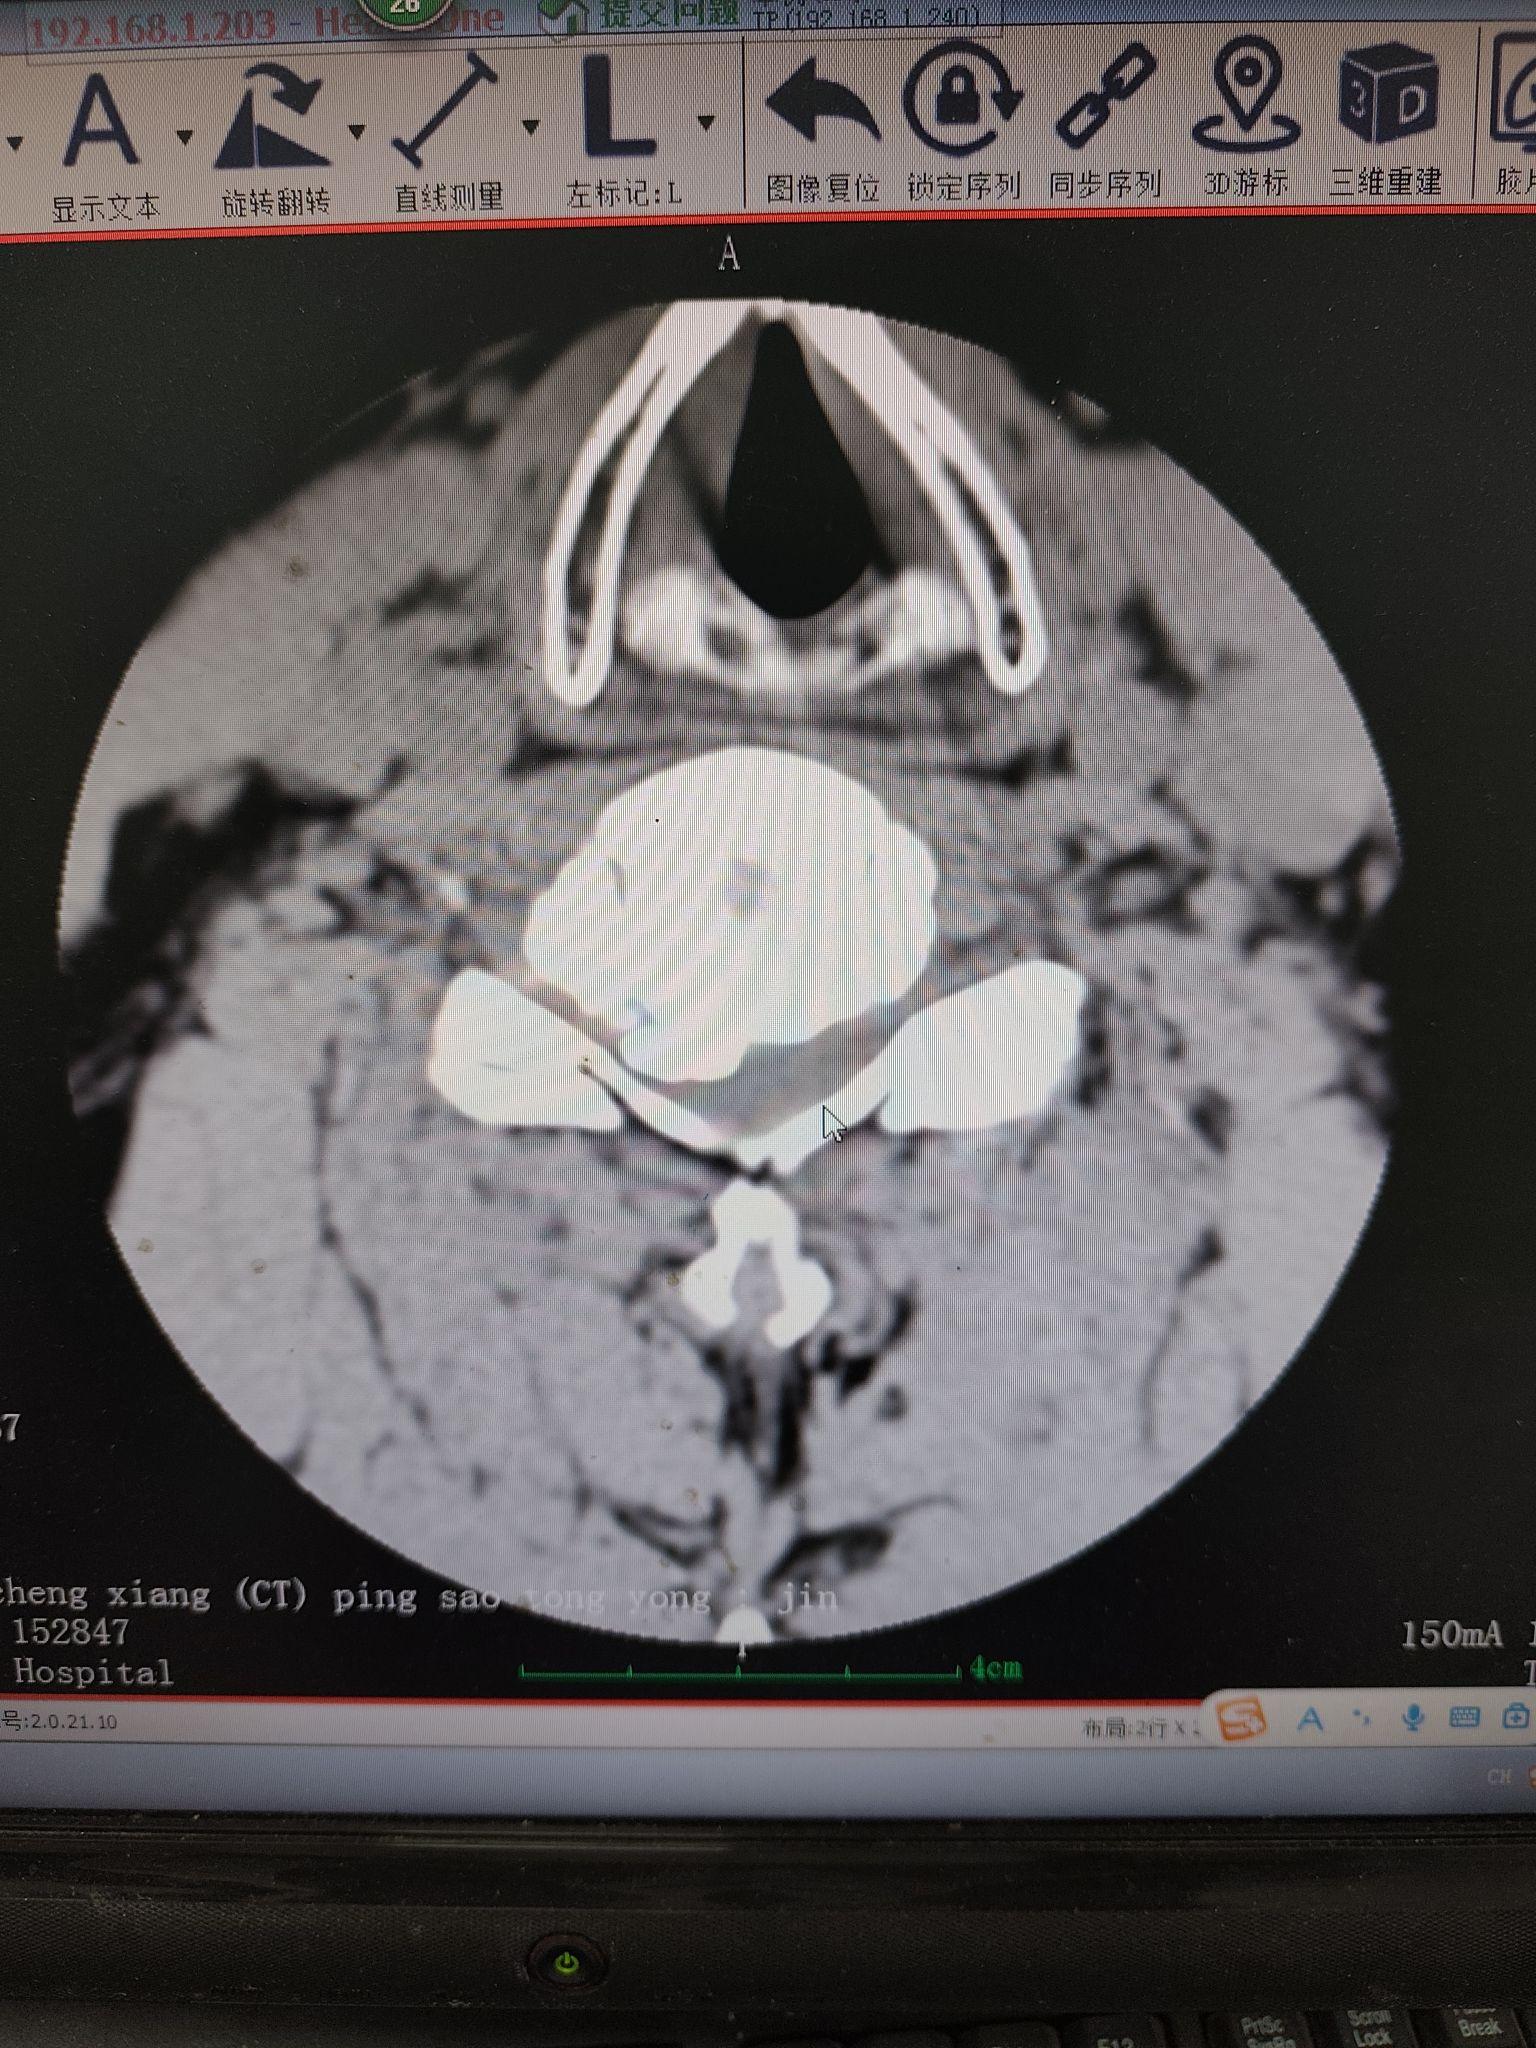

颈椎间盘突出,椎管狭窄